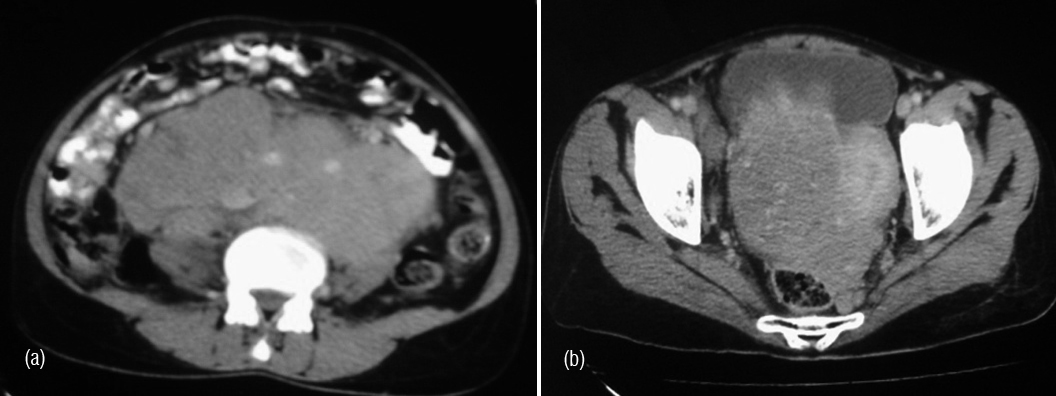

Ovarian cystic teratoma contains mature epithelial elements such as sebum, hair, epithelium, calcium, desquamated skin, and other elements which give complex appearance. Although they do not contain fat, they contain sebum which is lipid material with characteristic signal similar to fat. This differentiates it from other masses (Figures 11, 12, 13ab & 14).

Figure 14a,b,c: Mature cystic teratoma of the right ovary.